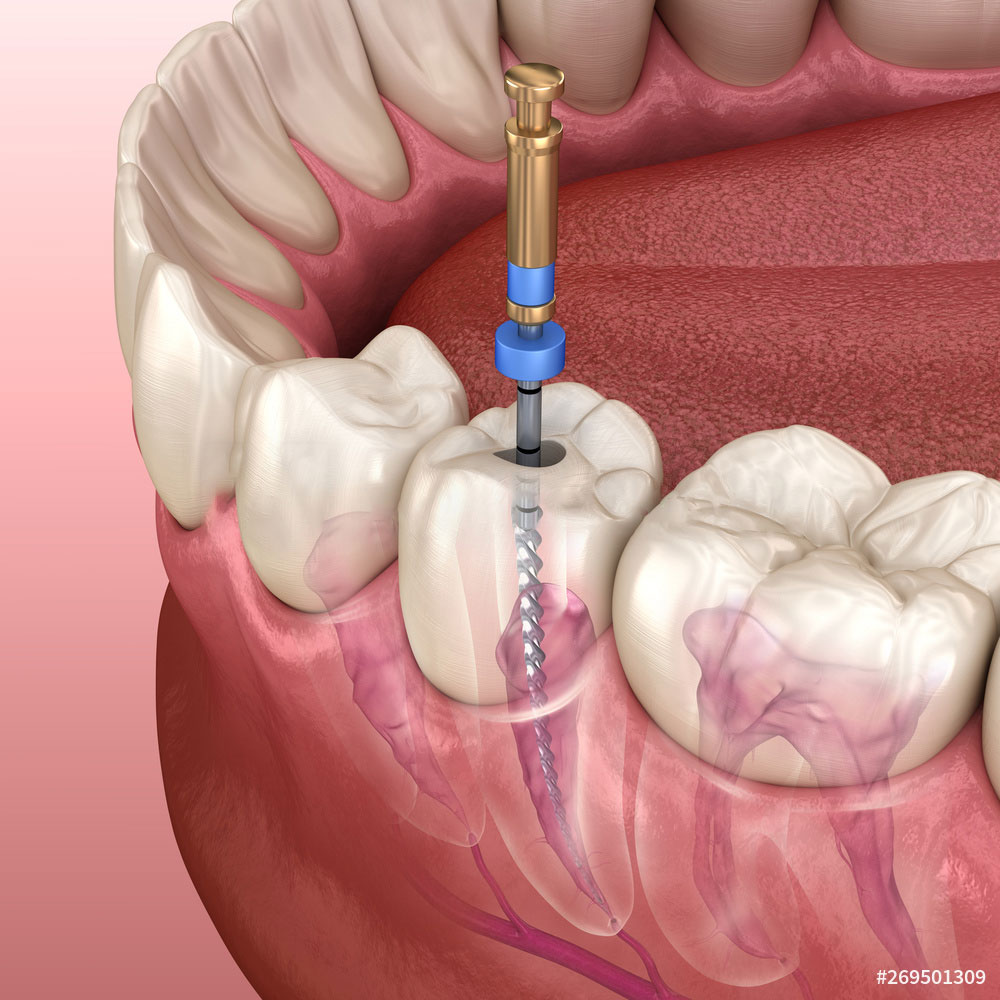

Root canal is a treatment to repair and save a badly damaged or infected tooth instead of removing it.